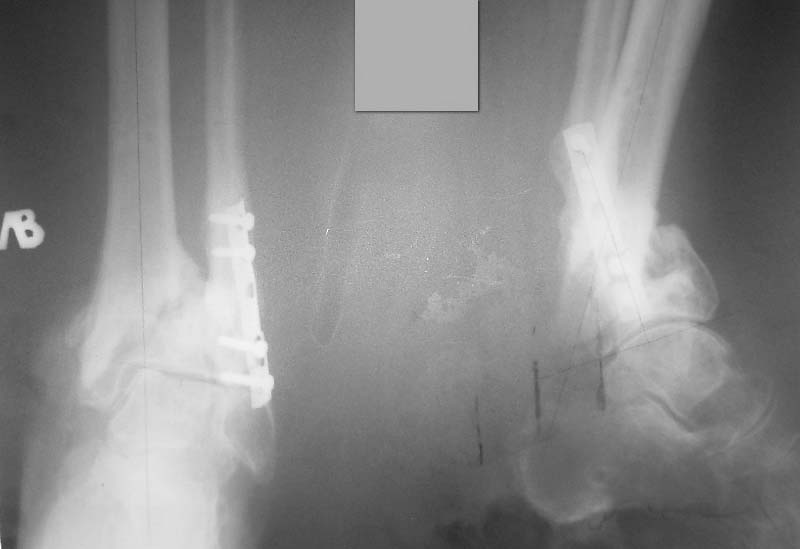

Частота ложных суставов и повторных смещений костных отломков после оперативной стабилизации переломов пилона доходит до 30%. Каждый, кто занимается лечением таких повреждений, наверняка сталкивался с такими осложнениями. Однако лечить такие осложнения в моральном, да и в оперативном плане проще, чем свежие переломы пилона (особенно Ruedi III), поскольку к этому времени становится более или менее понятной судьба голеностопного сустава. Если в достаточной мере владеете блокированным остеосинтезом, то самым оптимальным вариантом, с моей точки зрения, будет следующий. С переднемедиального и латерального доступов выполнить поперечную остеотомию большеберцовой и малоберцовой костей в плоскости параллельной плоскости голеностопного сустава на расстоянии около 3 см от самого сустава. Это минимальное расстояние, которое позволит расположить три блокирующих винта стержня. Важен выбор самого стержня. В данном случае больше всего подходит стержень ChM, имеющий на дистальном конце помимо отверстий в сагиттальной и фронтальной плоскостях и отверстия под углом в 45 градусов, причём на минимальном расстоянии друг от друга. Остетомию и последующую репозицию костных отломков мы выполняем в репозиционном спицевом аппарате. Стержень антеградный. В данном случае не вижу никаких оснований в применении ретроградного стержня, проходящего через здоровый подтаранный и через голеностопный сустав с его до конца неопределённой функцией. Образовавшийся дефект по переднемедиальной поверхности должен быть заполнен костным трансплантатом. Пример похожего случая из нашей практики - в приложенном файле.

Красивый пример, но только к данному случаю не очень-то применим. Другой характер смещения, совсем не такой дистальный фрагмент большеберцовой кости.

Дистальный фрагмент должен быть интересен только в плане его величины (которая регулируется уровнем остеотомии) и способности прочно удерживать блокирующие винты стержня. Безусловно, возникнут трудности при репозиции отломков после остеотомии. Критерий репозиции – проекция центра костномозгового канала проксимального отломка на середину суставной поверхности большеберцовой кости в обеих плоскостях при отсутствии угловых деформаций. И трудность не столько в репозиции, сколько в удержание отломков в репонированном положении на время введения, блокирования стержня и рентгенконтроля. Поэтому мы выполняем такие операции в репозиционном аппарате.

Уважаемый VlaD! А что значит синяя стрелка на Вашей презентации? Проведение одного блокирующего винта через обе кости это принципиальный момент операции?

Слайд взят из собственной презентации по лечению переломов пилона. При переломах пилона в большинстве случаев больше всего подвергается разрушению переднелатеральная и латеральная часть большеберцовой кости из-за вальгусной установки пяточной кости и флексии стопы во время травмы. Поэтому самый дистальный винт, который располагается во фронтальной плоскости, мы, путём ротации стержня, стараемся провести и в малоберцовую кость, чтобы конец блокирующего винта располагался в прочной кости и выполнял свою функцию. Не знаю, насколько это принципиально, но так как обе кости связаны между собой синдесмозом, наверное, в этом есть рациональное зерно.